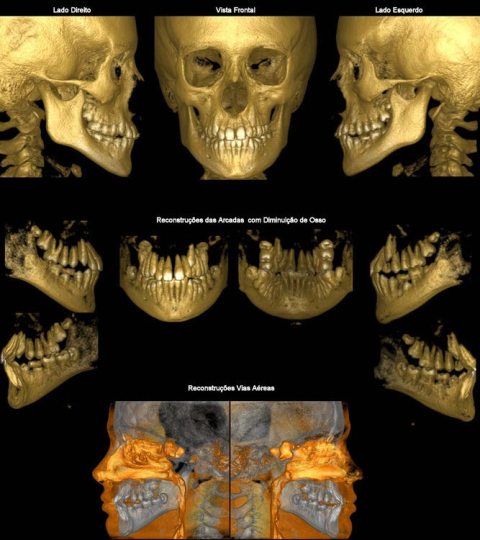

CASO 1 - Anquilose de ATM

Paciente com assimetria, limitação de abertura bucal. Observa-se união óssea da porção posterior e lateral do côndilo ao esfeóide e zigomático.

CASO 3 - Fratura de ATM

Paciente com história clínica de trauma. Fratura no côndilo direito com deslocamento do fragmento para medial e deslogamento do côndilo para lateral da cavidade articular.

CASO 4 - Lesão Patológica

O exame tomográfico permite a exata localização e extensão do tumor bem como a identificação de áreas com destruição da cortical e a localização de lesões satélites.

CASO 5 - Dente Retido

Dente 47 e 48 retidos, em posição mésio horizontal, sobrepostos com raízes superpostas ao canal mandibular. Ao exame tomográfico identifica-se o canal passando rechaçado entre os ápices do 48 e a cortical vestibular e passando entre as duas raízes mesiais do dente 47.

CASO 7 - Perda Óssea

Exame tomográfico de rotina para estudo de implante em áreas edêntulas posteriores. Observa-se perda da cortical vestibular no dente 41.